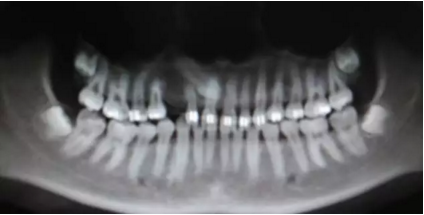

再看看逆襲的尖牙阻生。。。

小泥鰍

16.png

橫位

17.png

18.png

錯(cuò)位

19.png

大尺度異位

20.png